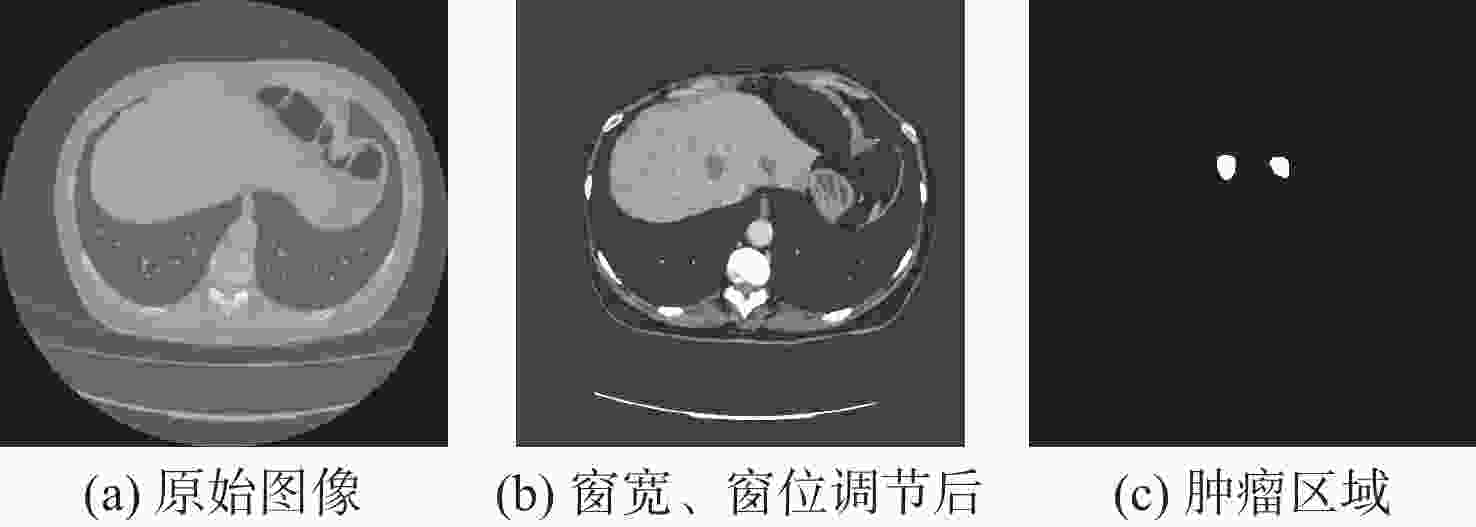

针对肝脏肿瘤检测中多尺度特征表达能力不足的问题,提出一种融合重参数化卷积、加权双向特征金字塔和注意力机制的肝脏肿瘤CT图像检测方法。使用数据增强改善样本量较少的问题,提高模型的泛化能力;使用加权双向特征金字塔网络融合图像的浅层与深层特征,提高多尺度特征的提取能力;在特征融合中引入无参数平均注意力模块,关注肝脏肿瘤的关键特征;使用重参数化卷积和边界框(SIoU)损失函数提高肿瘤的检测和定位能力。实验结果表明:所提方法在LT3DM和LiTS2017数据集上的平均精度均值(mAP)分别达到了92.9%和92.2%,比YOLOv5模型提高了2.3%和1.8%,相较于主流检测模型,所提方法具有更好的肝脏肿瘤检测能力。

Abstract:To address the problem of insufficient multi-scale feature representation in liver tumor detection, we propose a liver tumor CT image detection method that integrates reparameterized convolution, weighted bidirectional feature pyramid, and attention mechanism. Firstly, data augmentation is used to improve the problem of small sample size and enhance the generalization ability of the model. Secondly, to enhance the ability to extract multi-scale features, the weighted bidirectional feature pyramid network is utilized to merge the image's shallow and deep features. Then, a parameter-free attention mechanism is introduced in feature fusion to focus on the key features of liver tumors. Finally, reparameterized convolution and shapeaware intersection over union (SIoU) loss functions are used to improve tumor detection and localization accuracy. The mean average precision(mAP)of this method on LT3DM and LiTS2017 datasets reached 92.9% and 92.2%, respectively, which is 2.3% and 1.8% higher than that of the YOLOv5 model. The experimental results indicate that this method has a greater ability to detect liver tumors than standard detection models.